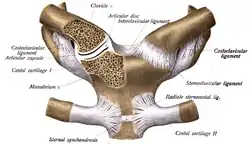

L'extrémité sternale est arrondie de la clavicule s'articule avec le manubrium sternal[5]. Ce couple forme, avec le premier cartilage costal, l'articulation sterno-claviculaire qui dispose de trois degrés de liberté (énarthrose). L'ensemble est solidement fixé par quatre ligaments[6].

- Articulation sterno-claviculaire :

- les ligaments antérieur et postérieur,

- le ligament costo-claviculaire qui relie la clavicule à la première côte,

- le ligament interclaviculaire qui unit les extrémités sternales des clavicules.